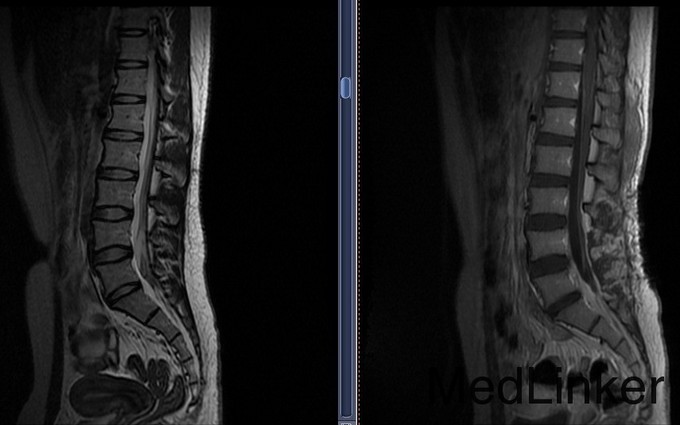

患者,女,F,19岁。以“腰腿痛20余天,缓解10天”为主诉入院。患者于20余天前无明显诱因突发腰部伴双下肢疼痛,疼痛呈阵发性,发作无规律,活动时加重,休息可缓解.无麻木和四肢无力等伴随症状.患者于2015年9月10日就诊于XX中心医院,行腰椎CT、腰椎MR及腰椎增强MR检查,提示L5水平椎管内异常强化灶。未予治疗。近10天,患者疼痛症状明显缓解。患者为求治疗,今日来我院,门诊以“腰椎管内占位”为诊断将患者收入我科。患者患病以来,精神状态可,饮食睡眠可,二便正常,体重无明显变化。

入院查体:T 36.5℃,P 90次/分, BP 116/70mmHg, R18 次/分.神志清,查体合作,营养发育良好,步入病房,浅表淋巴结未触及肿大.头颅大小正常,双瞳孔等大正圆,对光反射灵敏。四肢活动自如,肌张力正常,双上肢肌力V级,双下肢肌力IV,深浅感觉未见明显异常,双侧巴氏征阴性。Romberg征(-)。外院MR增强提示:L5水平椎管内异常强化灶。

患者病史较短,仔细追问腰痛期间曾有发热,科内讨论会诊不除外炎症或出血机化。安排手术后暂停,经过再次讨论和家属交待手术风险后决定手术探查。 腰后正中入路,椎管内占位病变探查切除术; 原手术方案拟行椎弓根固定,但术中病理提示不除外脊索瘤,考虑术后可能需放疗,遂放弃固定治疗。 术后石蜡病理为粘液乳头型室管膜瘤(WHOⅠ级)

随访:患者术后复查MR肿瘤完整切除,2周顺利出院,无运动、感觉及二便副损伤。 讨论:1.患者年轻女性,反复发热腰痛起病,病史不长,此类椎管内异常影像应考虑到炎症、出血等良性疾病可能,在充分向家属告知基础上方可手术探查。否则易出现纠纷。2.室管膜瘤(WHOⅠ级)多数预后良好,可不行后续放化疗,嘱患者定期门诊随访。